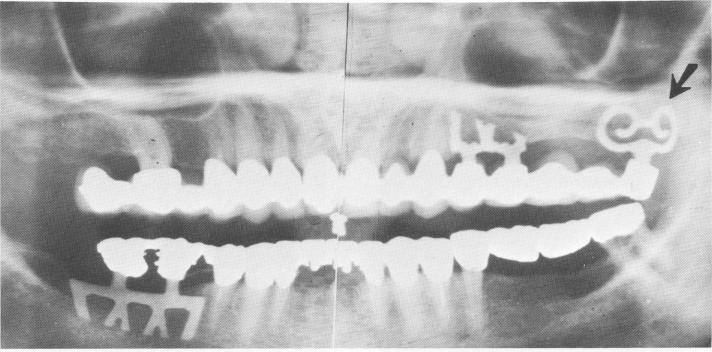

Fig. 11-204. This Panorex shows how three different blade designs suit their locations. The left maxillary tuberosity contains a curved blade (arrow) to obtain maximum metal-to-bone contact in a minimum amount of bone.

1 Panorex shows how three different blade designs suit their locations